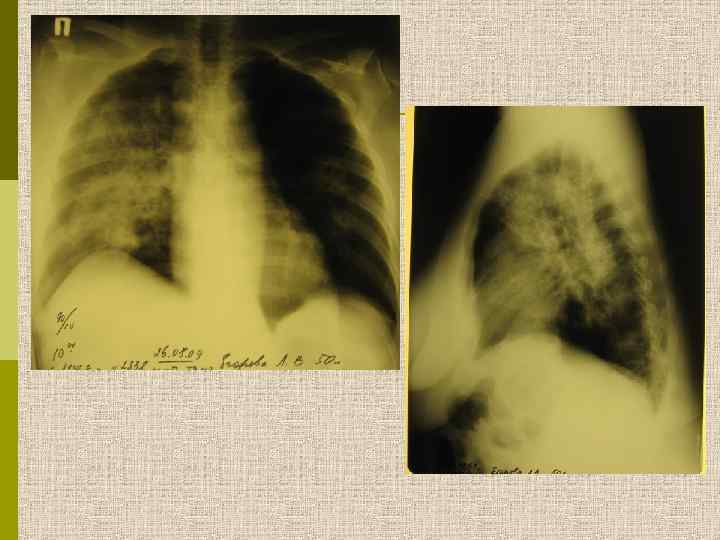

Легочные симптомы при микроскопическом полиангиите Атрофия мышц правой кисти Альвеолярная геморрагия правого легкого